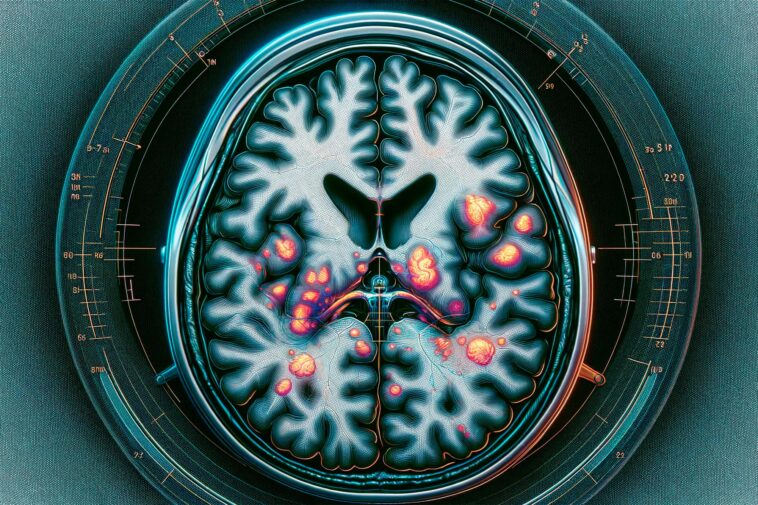

Une étude utilisant l’IRM de diffusion avancée a révélé des différences structurelles dans la substance blanche du cerveau des patients présentant des symptômes à long terme du COVID-19, suggérant une cause potentielle de leurs problèmes neurologiques persistants. Crédit : Issues.fr.com

Dans leur étude actuelle, les chercheurs ont donc ajouté un nouveau type d’imagerie par résonance magnétique appelée IRM de diffusion avancée. Ils se sont particulièrement intéressés à la substance blanche du cerveau. Celui-ci est principalement constitué d’axones nerveux et est très important pour transporter les signaux entre les différentes parties du cerveau et le reste du corps.

Les utilisations médicales de l’IRM de diffusion comprennent le diagnostic des accidents vasculaires cérébraux et la planification d’une chirurgie cérébrale. Dans leur étude actuelle, les chercheurs ont utilisé une version plus avancée de l’IRM de diffusion. Ils ont examiné 16 hommes qui avaient été hospitalisés pour un COVID-19 grave et qui participent à l’étude Linköping COVID-19 (LinCos) au département de médecine de réadaptation de Linköping. Ils présentaient encore des symptômes persistants après sept mois. Ce groupe a été comparé à un groupe d’individus en bonne santé sans symptômes post-COVID qui n’avaient pas été hospitalisés pour COVID. Les cerveaux des participants ont été examinés à la fois par IRM conventionnelle et par IRM de diffusion.

« Les deux groupes diffèrent en ce qui concerne la structure de la substance blanche du cerveau. Cela peut être l’une des causes des problèmes neurologiques rencontrés par le groupe qui a souffert d’une forme grave du COVID-19. C’est un résultat qui concorde avec d’autres études qui ont montré des changements dans la substance blanche du cerveau. Cependant, n’ayant examiné qu’un petit groupe de patients, nous sommes prudents avant de tirer des conclusions majeures. Avec cette technologie, nous ne mesurons pas la fonction du cerveau, mais sa microstructure. Pour moi, ces résultats sont le signe que nous devons étudier les effets à long terme du COVID-19 sur le cerveau en utilisant une technologie d’IRM plus avancée que l’IRM conventionnelle », explique Ida Blystad.

Les chercheurs souhaitent approfondir plusieurs questions. Il semble, par exemple, que la substance blanche dans différentes parties du cerveau soit affectée de différentes manières, bien qu’il soit trop tôt pour tirer des conclusions sur la signification de ces différences. Une étude à venir examinera si les changements détectés par l’IRM de diffusion sont liés d’une manière ou d’une autre à l’activité cérébrale et comment différentes parties du cerveau communiquent entre elles via la substance blanche du cerveau chez les patients souffrant de fatigue post-COVID.